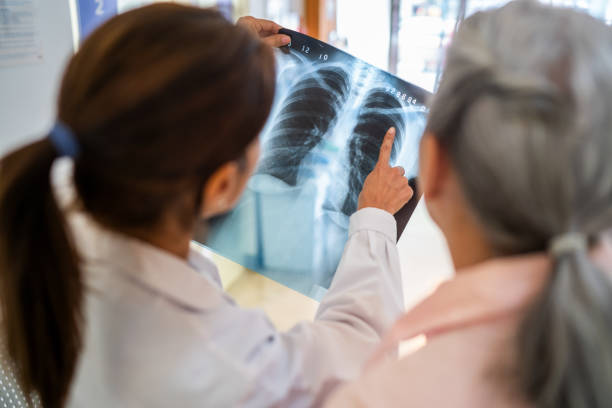

흉부 X-ray와 CT 검사

폐섬유증 초기에는 일반 흉부 X-ray에서 정상처럼 보일 수 있어 진단이 쉽지 않습니다. 그러나 고해상도 CT(High Resolution CT)를 통해 폐 조직의 섬유화 진행 정도를 더 정밀하게 확인할 수 있습니다. 따라서 폐섬유증 초기증상이 의심된다면 CT 검사가 중요합니다.